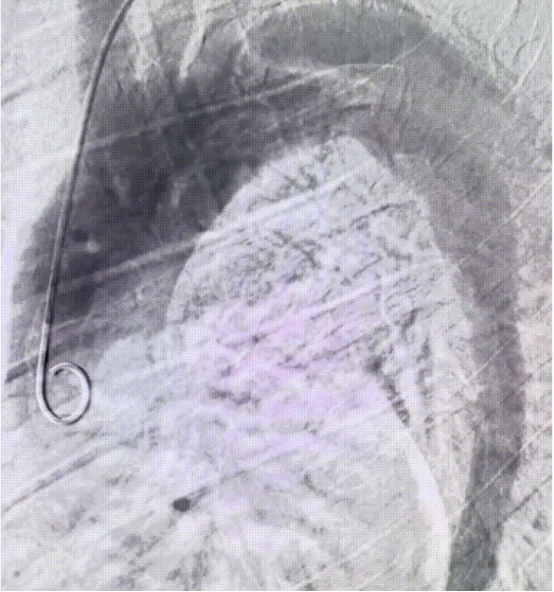

术前DSA

沿导丝推送主体支架至预期位置,造影显示定位精准